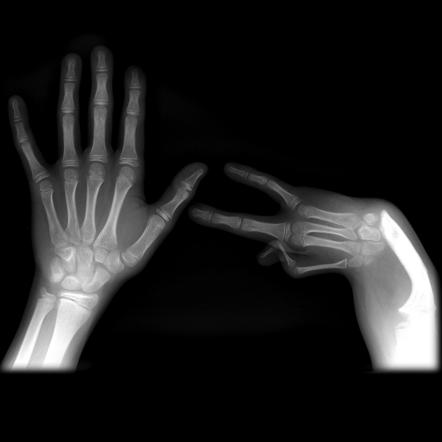

Креативные рентген-снимки рук с изображением сердечка

Раздел: Необычные решения